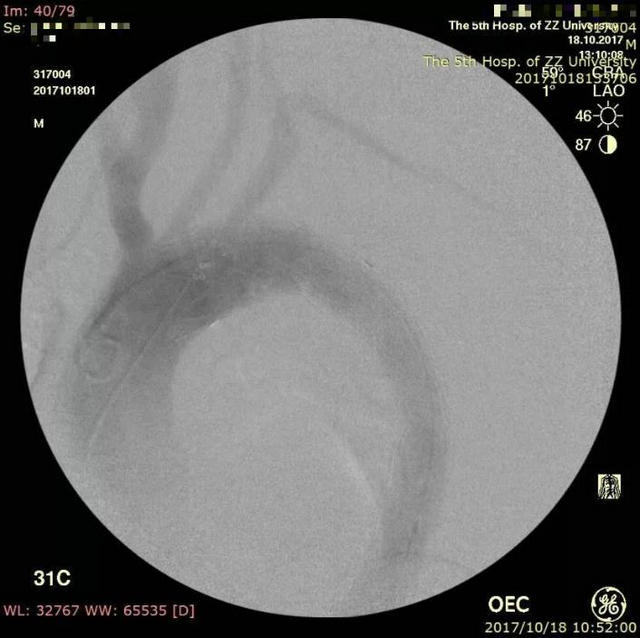

▲ 造影显示胸主动脉夹层

▲ 主动脉覆膜支架放置后左锁骨下动脉不显影